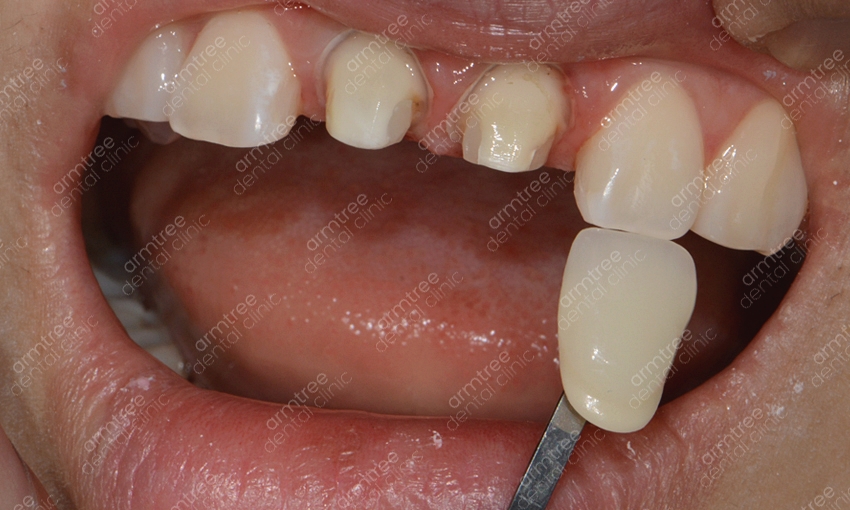

신논현역 치과 아름드리치과에서 실활치미백을 진행하는 과정을 알려드릴께요. 먼저 치아 내부의 신경과 혈관 등이 괴사한 경우라면 신경치료를 우선적으로 진행해요. 신경치료를 마무리 한 후 입술보호제를 꼼꼼히 발라주고 신경 쪽을 막은 뒤 미백제를 투여하는 과정을 진행해요. 충전된 미백제 입구를 막고 상태를 지켜본 뒤 간격을 두고 미백약제를 교체하여 몇 번의 과정을 반복해주어요. 물론 개인차가 존재하지만 대략 2-3회 정도 반복 과정을 한 뒤 미백이 완료되면 입구를 레진으로 수복하여 마무리를 해요. 치아미백을 하시고 난 후 외관상으로 다른 부작용은 없으나 간혹 약간의 시림증상이 발생할 수 있는데요. 하지만 일정 시간이 지나면 곧 괜찮아 지며 변색의 정도가 심해 미백으로 개선이 어려울 시 라미네이트도 대안이 될 수 있다는 걸 알아두세요. 앞니변색으로 인하여 미백을 진행할 경우 하얀 치아로 개선하는 것도 중요하겠지만 다른 치아와의 컬러 밸런스가 필요해요. 하나만 홀로 하얗다면 검거나 누런 것과 비슷하게 심미적으론 좋지 않기 때문에 색상 조절을 잘 해줄 수 있는 전문적인 의료기관을 선택해야 하겠어요.